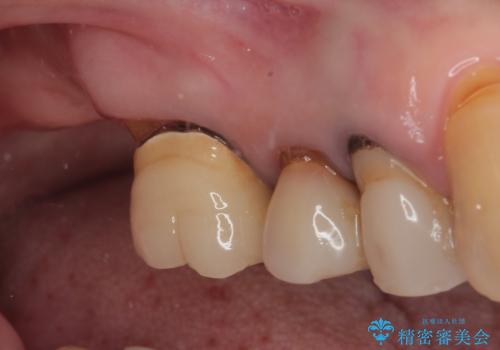

抜歯後2ヶ月でのインプラント埋入を行いましたが、骨の再生は不十分でした。

骨量は不十分でしたが、デンサーバーを用いることで無事に埋入することができ、その後は速やかに補綴治療を行うことができました。